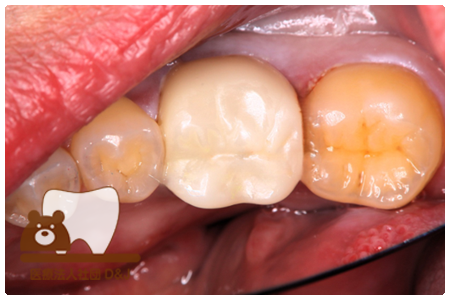

症例3フリジルコニアクラウン 左上6

治療前

治療後

59歳 男性

- 治療内容

- 虫歯で大きく失われた歯に対して、土台としてファイバーコアを使用し、その上にフルジルコニア製の被せ物を装着しました。見た目と強度を両立した自由診療の治療です。

- 治療期間

- 根の治療含めて3カ月半

- 費用

- 自費

フリジルコニアクラウン:77,000円(税込)

(R8.2月時点)

- その他の治療の費用は含まれておりません。

- リスク・副作用

- 強い力が加わると割れる可能性があります。また、噛み合わせや歯ぎしりの影響で脱離することがあります。